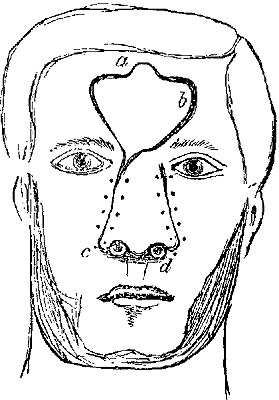

The four plates which precede the letterpress were drawn on wood (from original photographs) by Mr. D.W. Williamson, Melbourne Place, and the lines of incision for the various operations were added by the author.

The rough woodcuts scattered through the work were drawn on wood by the author, and for their roughness he, not his engraver, is responsible. He also hopes that the references in the letterpress will be accepted as sufficient acknowledgment of the true ownership, in those few instances in which the idea of the diagram has been borrowed.